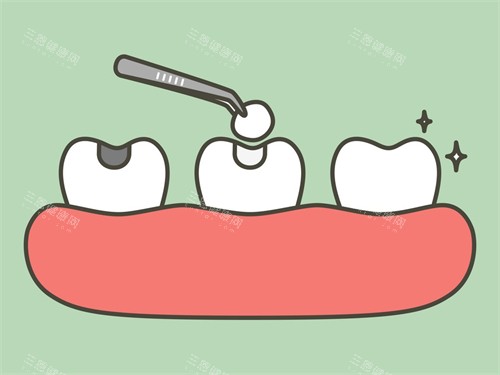

拍牙片的过程也特别快,就在诊室旁边的房间,机器是那种智能化的,不用等很久就能出结果。张医生拿着片子给我仔细讲解:“你看这里,蛀洞已经快到牙本质深层了,好在还没伤到牙髓,不用做根管治疗,补一下就行。”他还特意指给我看正常牙齿和蛀齿的区别,告诉我平时要多注意清洁邻面,不然很容易藏食物残渣。

清理完蛀洞后,张医生给我看了几种补牙材料,有树脂的、玻璃材料的,还有进口的纳米树脂。他详细介绍了每种材料的优缺点:“树脂材料颜色和牙齿很接近,硬度也够,适合补后牙;玻璃材料对牙齿刺激小,适合儿童或者敏感牙;进口纳米树脂更耐磨,使用寿命更长。”他还根据我的情况推荐了树脂材料,说性价比较高,价格也在我的预算范围内。

选好材料后,张医生就开始填充了。他特别细致,填充完还会用工具一点点塑形,打磨,直到和我的牙齿形状完全贴合。补完后,他让我咬合几下,问我“有没有高低不平的感觉?”,调整到合适的高度后,又用光照固化,整个过程大概也就二十多分钟。